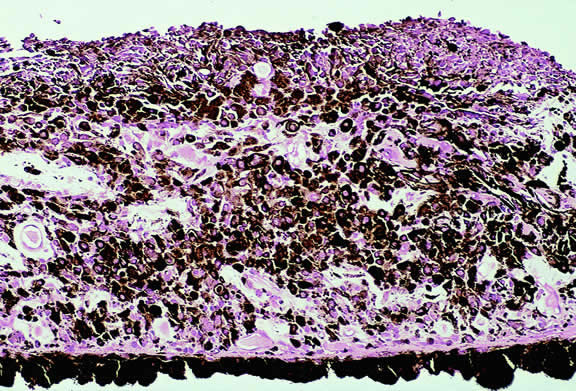

Nucleolar parameters also have been assessed with the silver-stained nucleolar organizer region (AgNOR) technique that examines nucleolar organizing regions that have been stained with colloidal silver azotate.116–119 Spindle, mixed, and epithelioid melanomas were found to have progressively larger mean AgNOR values.117 and the COMS group showed that malignant lesions have higher mean AgNOR counts (4.347) than benign nevi119 (1.855). Automated image capture and analysis has been performed on melanomas stained with the AgNOR technique.116